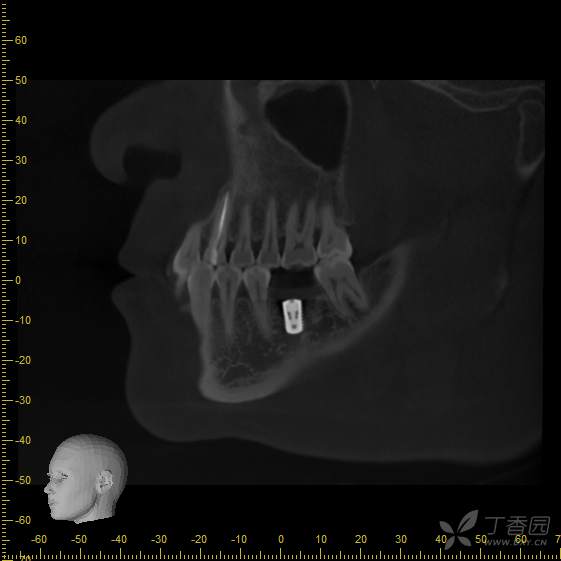

手术后3个月,可见种植体周围骨结合良好,行软组织成形(即二期),局麻下更换愈合帽。

戴牙后3个月,患者自述吃东西时疼痛,种植牙出现松动。

接诊时,36种植牙松1-2°,颊侧牙龈未见明显红肿。拍摄cbct后可见种植体周骨结合丧失,大量低密度影,骨吸收至根尖1/3,种植体浮出。